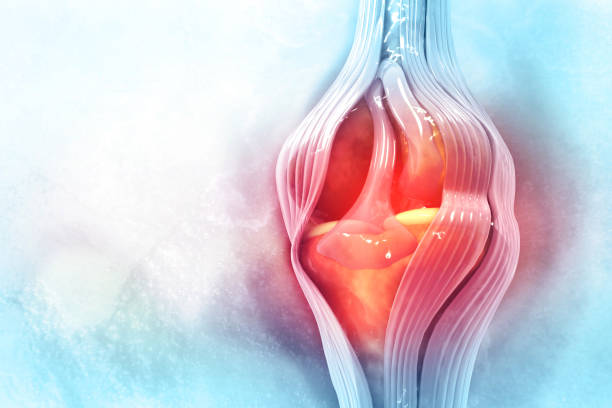

연골은 뼈와 뼈 사이의 마찰을 줄이고 충격을 흡수하는 기능을 합니다. 무릎의 연골손상은 무릎 통증의 일반적인 원인 중 하나입니다. 연골손상은 다양한 원인으로 발생할 수 있으며, 가장 흔한 원인은 무릎 관절 내의 충격이나 비대칭적인 압력에 의해 발생하는 외상입니다. 연골손상은 통증, 부종, 불안정성, 감각 손실 등의 증상을 일으킬 수 있습니다. 치료는 무릎 관절을 안정시키는 운동, 연골 재생을 촉진하는 약물 치료, 수술 등이 있습니다.

전방십자인대 파열에 의한 무릎 통증

전방십자인대는 무릎을 지탱하는 중요한 인대 중 하나입니다. 이 인대가 파열되면 무릎이 불안정해지며, 걷거나 달리는 등의 운동 시 무릎이 흔들리거나 무력감이 느껴집니다. 무릎 통증, 부종, 불안정감 등의 증상이 나타나며, 복합적인 치료가 필요합니다. 치료에는 수술적 치료, 전문가의 지도하에 진행되는 재활 운동 등이 포함됩니다.